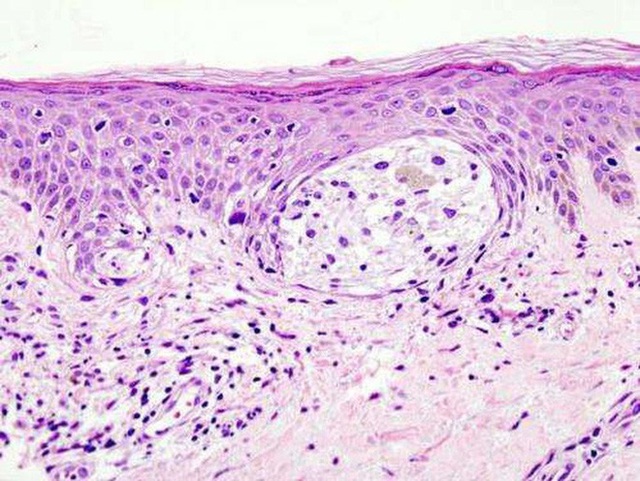

Cận cảnh các tế bào ung thư hắc tố - ảnh: MEDICAL XPRESS